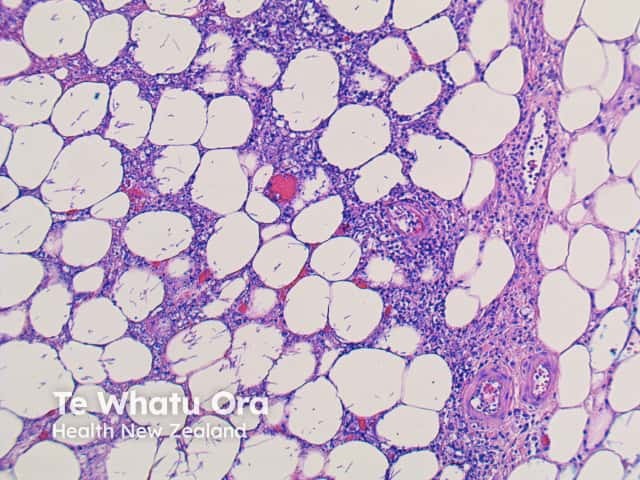

The inflammatory pattern to the fungal forms of aspergillosis depends on the depth of invasion and the immune status of the patient.

More commonly, there is a dense acute infiltrate in the dermis and deep soft tissue (figures 3, 4) which may be associated with necrosis and scarring. The organisms may sometimes be seen on close examination with routine H-E staining (figures 2, 4). With special stains, the morphology is better appreciated and shows thin, septate hyphae with regular branching (figures 5, 6). The angle of the regular branching is approximately 450 (figure 5, arrow).

There may be angioinvasion, ulceration and extensive necrosis. In immune competent patients, a dense granulomatous response is common. Direct skin inoculation can cause a marked epidermal response.